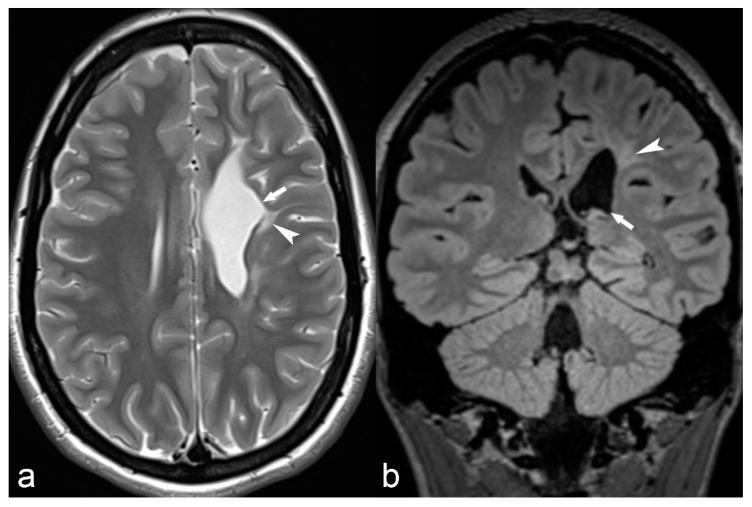

The etiology of epilepsy is variable and sometimes multifactorial. Clinical course and response to treatment largely depend on the precise etiology of the seizures. Along with the electroencephalogram (EEG), neuroimaging techniques, in particular, magnetic resonance imaging (MRI), are the most important tools for determining the possible etiology of epilepsy. Over the last few years, there have been many developments in data acquisition and analysis for both morphological and functional neuroimaging of people suffering from this condition. These innovations have increased the detection of underlying structural pathologies, which have till recently been classified as "cryptogenic" epilepsy. Cryptogenic epilepsy is often refractory to anti-epileptic drug treatment. In drug-resistant patients with structural or consistent functional lesions related to the epilepsy syndrome, surgery is the only treatment that can offer a seizure-free outcome. The pre-operative detection of the underlying structural condition increases the odds of successful surgical treatment of pharmacoresistant epilepsy. This article provides a comprehensive overview of neuroimaging techniques in epilepsy, highlighting recent advances and innovations and summarizes frequent etiologies of epilepsy in order to improve the diagnosis and management of patients suffering from seizures, especially young patients and children.